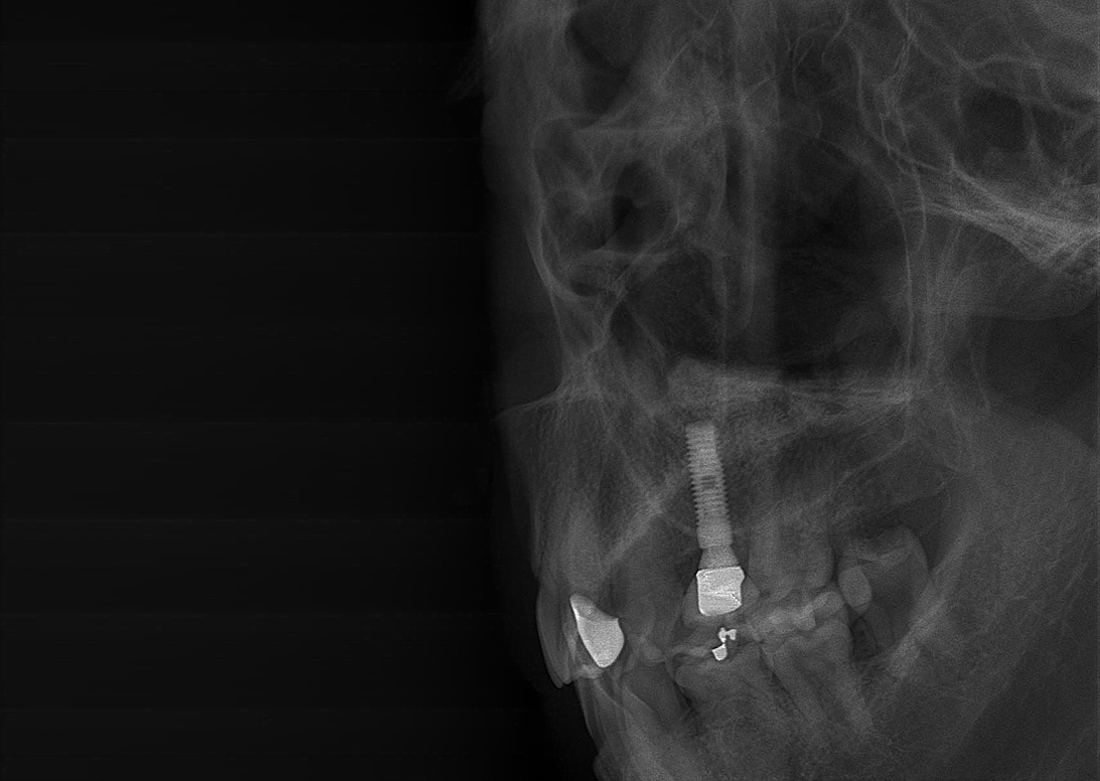

CUST (Cubical Semi Tomographic)

A CUST 256 keresztmetszeti felvétel felhasználásával készíti el az implantátum-diagnózishoz szükséges képeket. Gazdaságosabb megoldást kínál, mint a 3D CT.

KLİNIKAI KÉPEK

Kiváló diagnosztikai képalkotás több éves tapasztalattal és szakértelemmel.